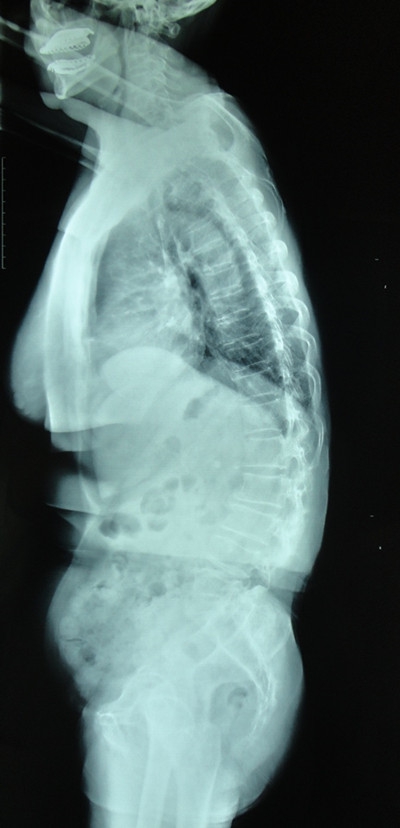

目前临床上最常用的判断矢状位平衡的方法为颈7铅垂线(C7PL, Cervical 7 Plumb Line)法。当C7PL位于骶骨后上角前方5cm以上时则定义为整体失平衡。而随着对参与矢状位平衡代偿机制的理解,颈7铅垂线法也存在一些不足之处。例如部分胸腰段后凸畸形的病人,临床症状很重,然而C7PL通过代偿机制却处在正常范围内。(图1)Roussouly等提出脊柱骶骨角(SSA, Spino-Sacral Angle)的概念,定义为C7椎体中点与骶骨平台中点连线和骶骨平台间所成的角,对于高加索人群正常值约135°。脊柱存在后凸畸形时,SSA值减小。该法也可快速、简便的辅助判断整体平衡,然而在国内还缺少相关报道。

图1.老年脊柱退变性胸腰段后凸畸形的患者,可见下腰椎L4/5、L5/S1间隙明显过伸,L4椎体轻度后滑脱,骶骨变平提示有骨盆后倾代偿,而胸椎的后凸亦明显减小。通过以上代偿方式,患者颈7铅垂线至骶骨后上角的距离约为5cm,整体并未出现明显失衡。